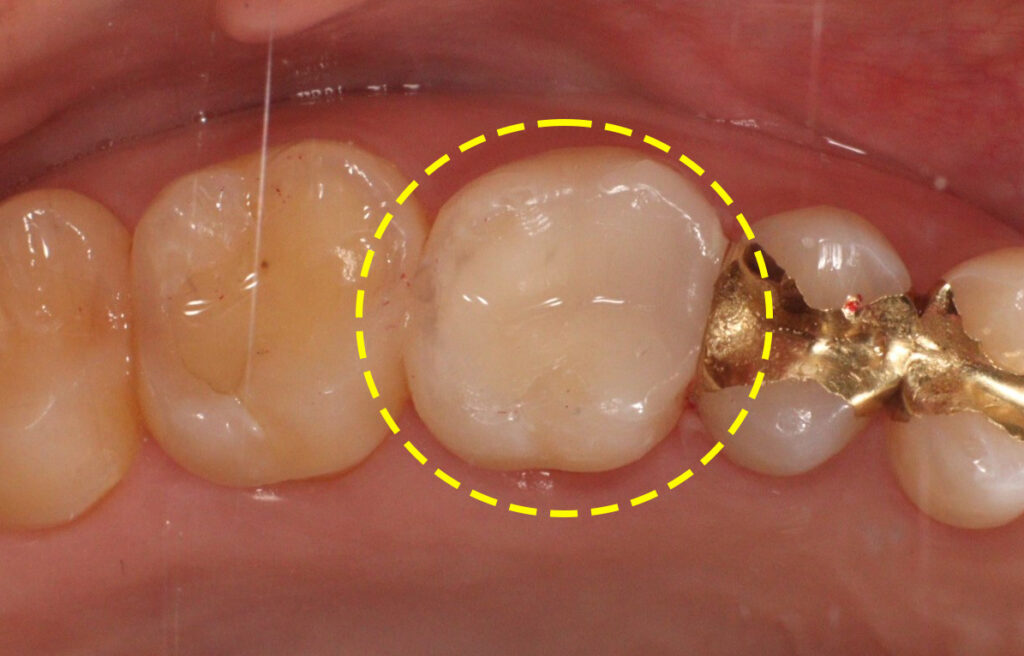

치아 내부를 정리한 후에는 남아있는

치질의 양과 교합 상태를 고려하여

수복 방법을 결정하게 됩니다.

이 경우 크라운 치료를 진행하기에는

삭제량이 과도해질 수 있어,

보다 보존적인 접근이 가능한

세라믹 인레이를 선택하였습니다.